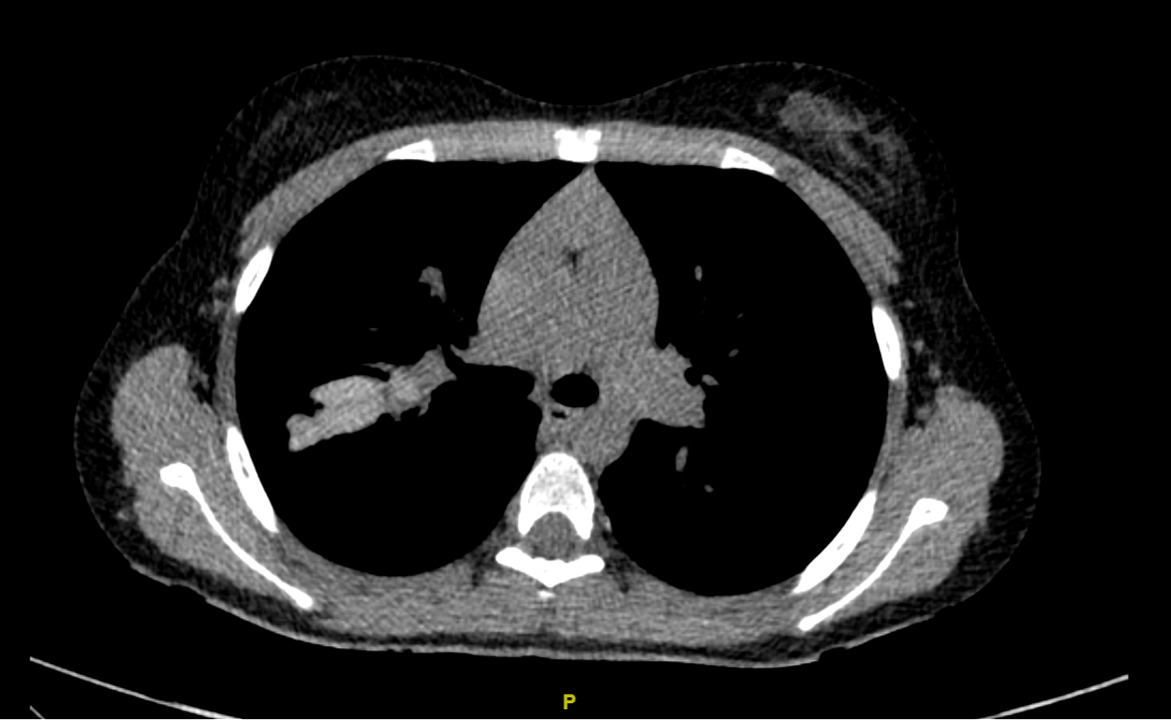

Quelques situations cliniques aiguës peuvent nécessiter la réalisation d’examens d’imagerie thoracique en urgence  : c’est le cas notamment des douleurs thoraciques aiguës et des hémoptysies. Le diagnostic d’exacerbation respiratoire ne nécessite le plus souvent pas le recours à des examens radiologiques, mais la non-réponse au traitement bien conduit peut justifier de réaliser une radiographie du thorax ou un scanner thoracique pour rechercher une explication telle que l’aspergillose bronchopulmonaire allergique. Dans ce cas, des signes radiologiques spécifiques peuvent être mis en évidence tels que l’inversion de contraste des impactions mucoïdes (fig. 2).6